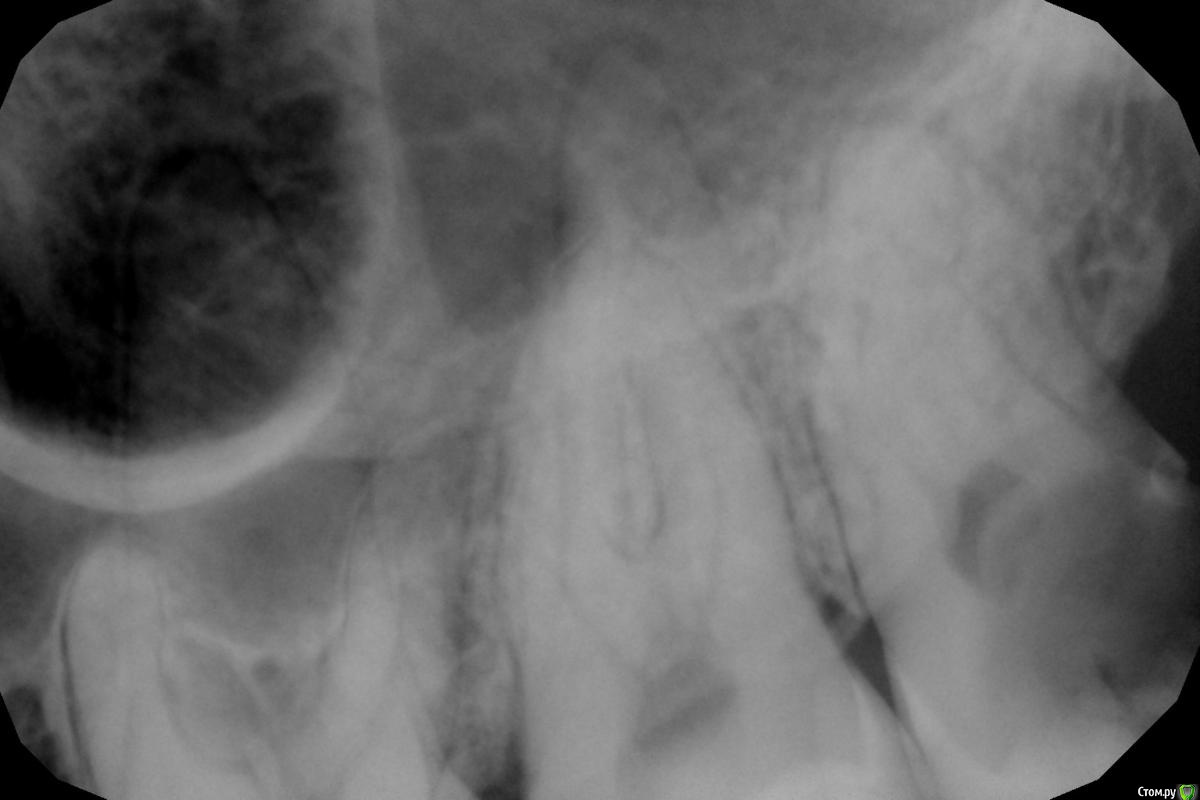

Аслан Опубликовано 23 июля, 2015 Поделиться Опубликовано 23 июля, 2015 http://s011.radikal.ru/i315/1507/20/52aed96012d9t.jpghttp://s017.radikal.ru/i424/1507/43/b96de6e42bddt.jpgВот такой красавец пришел.Отправил в члх, хотя самому было бы интересно удалить. пациент немного такой, что ни одно информированное может не спасти, хотя и реферативный, направлен другим доктором. Ссылка на комментарий

Доктор Добрых Дел Опубликовано 24 июля, 2015 Поделиться Опубликовано 24 июля, 2015 (изменено) Вот такой красавец пришел.Отправил в члх, хотя самому было бы интересно удалить. пациент немного такой, что ни одно информированное может не спасти, хотя и реферативный, направлен другим доктором.Недавно была похожая, тоже 48, только перфо кортикальной пластинки в язычную сторону, ну и не так глубоко сидела. Изменено 5 августа, 2015 пользователем IvanK Ссылка на комментарий